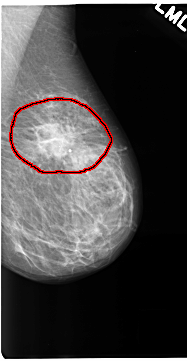

C_0123_1.RIGHT_MLO

LEFT_CC LINES 4688 PIXELS_PER_LINE 2544 BITS_PER_PIXEL 12 RESOLUTION 50 OVERLAY

FILE: C_0123_1.LEFT_CC.OVERLAY

TOTAL_ABNORMALITIES 1

ABNORMALITY 1

LESION_TYPE MASS SHAPE IRREGULAR MARGINS ILL_DEFINED

ASSESSMENT 5

SUBTLETY 5

PATHOLOGY MALIGNANT

TOTAL_OUTLINES 1

BOUNDARY